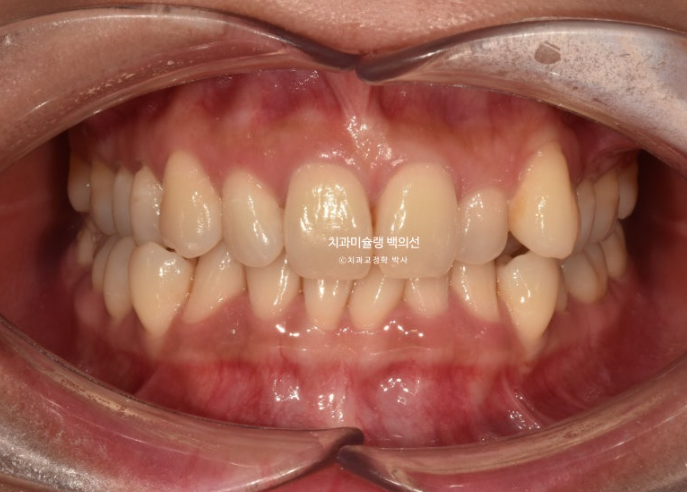

25.04

중심선이 맞아지고 과개교합도 해결되었고 아래앞니 치축 기울어짐이 보입니다.

덧니가 배열되며 반대교합도 해소가 되었습니다.

아래 앞니 배열이 약간 아쉽습니다.

이 부분들을 고치기 위해서 재제작에 들어갔습니다.

25.08

총 치료기간은 1년이고 재제작은 1회 했습니다.

교정치료의 완성은 예쁜 앞니와 어금니 교합입니다.

물샐틈 없는 교합이 되지 않으면 치료를 마무리 짓지 않습니다.